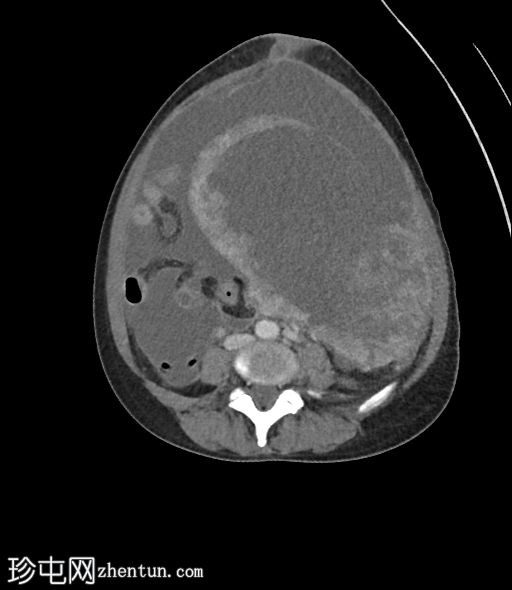

入院时CT检查

CT

1.jpg

腹部中部可见一巨大、不均匀、中心坏死的肿块。

中至大量腹水。

子宫肌瘤。